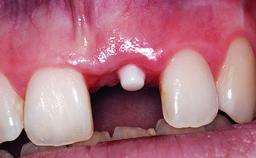

A 32-year-old female Caucasian patient with a compromised maxillary right central incisor was referred to us by a general dentist. Her chief complaints were discomfort and mobility of tooth 11 with unsatisfactory esthetics due to discoloration. The patient reported a previous trauma, some years earlier, as the origin of pathology on the afflicted tooth. Anamnesis was negative for any other dental or periodontal pathology in the remaining dentition. The patient did not take any medication and reported to be a light smoker (5–10 cigs/day). She had high esthetic expectations of her treatment. The extraoral examination revealed a high smile line with full exposure of her maxillary teeth and surrounding soft tissue in the area between the second premolars.

| # of Implants | 1 |

| Type of Implants | Reduced-Diameter|Two-Piece |

| Placement Protocol | Early or late implant placement |